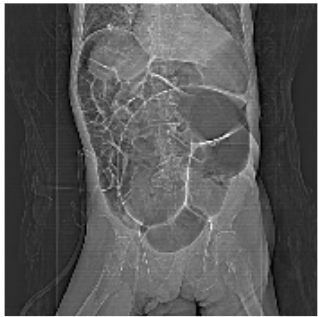

33. 五十歲阿嬤騎機車載三歲小男孩坐在前面,在十字路口被汽車從右方撞倒,緊急送醫後發現 阿嬤右大腿骨折,小男孩有右腹擦傷,小男孩受驚嚇不停哭鬧,全身冒汗,血壓95/55 mmHg,心跳數每分鐘130下,Hb 10.5 g/dL,電腦斷層檢查如下圖所示,下列敘述何者正 確?

(A)此幼兒為右腎撕裂傷 (B)幼兒有大量失血,需馬上輸紅血球補充 (C)若幼兒血行動力方面穩定(hemodynamic stable),可嘗試非手術(non-operative)的支 持療法 (D)此時宜進行緊急開腹手術